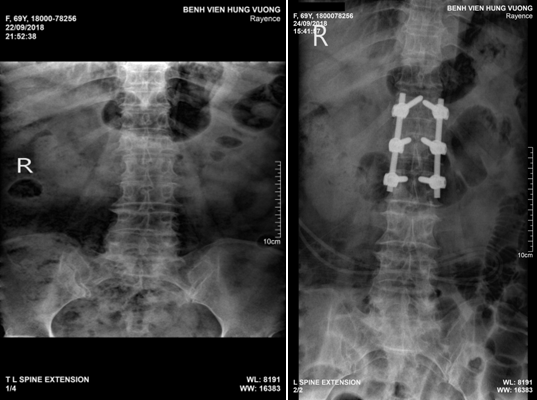

Tại đây, kết quả chụp CT đa dãy cho thấy hình ảnh tổn thương mất vững xẹp thân đốt sống L1, vỡ cung sau đốt sống, thoái hóa đa tầng cột sống thắt lưng.

Bệnh nhân được chỉ định phẫu thuật cố định cột sống L1, ghép xương với chẩn đoán chấn thương cột sống, vỡ đốt L1.

Hiện tại, chị H. được phẫu thuật cố định cột sống và ghép xương thành công.

Hình ảnh cột sống của chị H. trước và sau phẫu thuật. (Ảnh: Bệnh viện cung cấp)